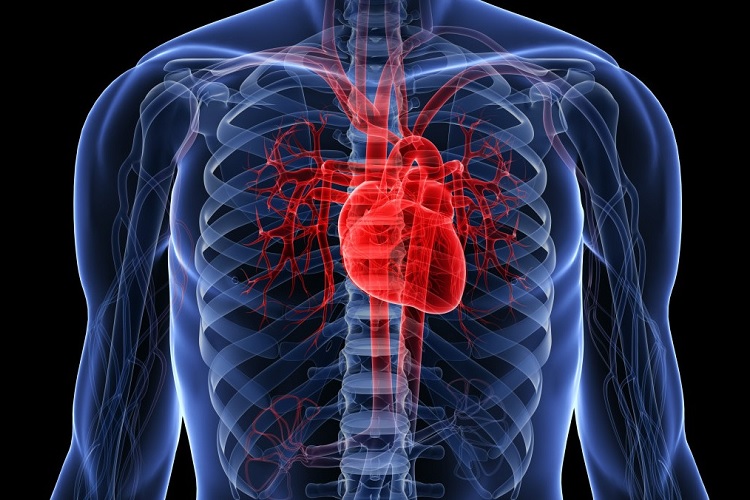

عکس اسکلت بدن انسان با کیفیت. عکس اسکلت عکس اسکلت برای پروفایل عکس اسکلت انسان عکس اسکلت خفن عکس اسکلت بدن انسان با کیفیت عکس اسکلت بدن انسان عکس اسکلت ترسناک عکس اسکلت فانتزی عکس اسکلت فانتزی دخترانه پرچم عکس اسکلت. عکس با کیفیت اسکلت داخلی انسان و درد و گرفتگی در ناحیه استخوان زانو ویژه استفاده در امور تبلیغاتی و تجاری طراحی کاتالوگ بروشور و تراکت با موضوع پزشکی فیزیوتراپی ارتوپد دکتر روماتیسم فیریوتراپ طب فیزیکی. عکس اسکلت بدن انسان زن و مرد آناتومی ساتین 16 سپتامبر 2017. اسکلت داربست بدن است تمام قسمت های بدن روی اسکلت قرارگرفته اند بدن انسان از ۲۰۶ قطعه استخوان تشکیل شده است این استخوان ها طوری با نظم کنار هم قرار گرفته اند که انسان را قادر می سازد حرکات دقیقی داشته باشد.

اسکلت جمجمه و گردن انسان ستون فقرات آناتومی اسکلت جمجمه و گردن انسان ستون فقرات آناتومی تصویر با کیفیت را از لینک زیر می توانید دانلود کنید. ۱ مطلب با کلمه ی کلیدی عکس اسکلت بدن انسان با کیفیت ثبت شده است گالری نسیم جدید ترین و با کیفیت ترین عکس های مناسبتی. عکس با کیفیت آناتومی اسکلت بدن انسان و درد و دیسک در قسمت مهره های ستون فقرات کمر ویژه استفاده در امور تبلیغاتی و تجاری طراحی کاتالوگ بروشور و تراکت با موضوع بیمارستان ها و کلینیک ها و درمانگاه ها و مطب ها پزشکان و.